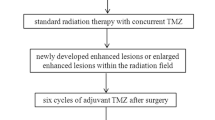

From January 2021 to September 2023, 21 patients (11 men and 10 women; age range 28–76 years) who were being treated for glioma were prospectively and consecutively enrolled. Inclusion criteria were:

-

Completion of standardized treatment, including gross total resection followed by radiation therapy and temozolomide chemotherapy.

-

Presence of a contrast-enhanced lesion with findings inconclusive of TR or PTC on follow-up MRI performed at least 3 months after radiation treatment.

-

No contraindications to undergo an MRI with contrast medium administration and an 18F-DOPA PET/CT examination.

The final diagnosis of TR or PTC was made based on radiologic and clinical evaluation with a final consensus decision made by a neuroradiologist (A.R. 15 years of experience) and a neurooncologist (A.M.A. 15 years of experience), both blinded to perfusion MRI and 18F-DOPA PET/CT data. Tumor recurrence was defined as a progressive increase in size, contrast enhancement, and mass effect despite steroid therapy in at least three subsequent MRI follow-up studies in an observational period of at least 9 months, in combination with deteriorating neurologic symptoms. Non-recurrence was defined on imaging as stable or resolving regions of enhancement over at least a 9-month observational period, accompanied by neurologic improvement during the follow-up period.